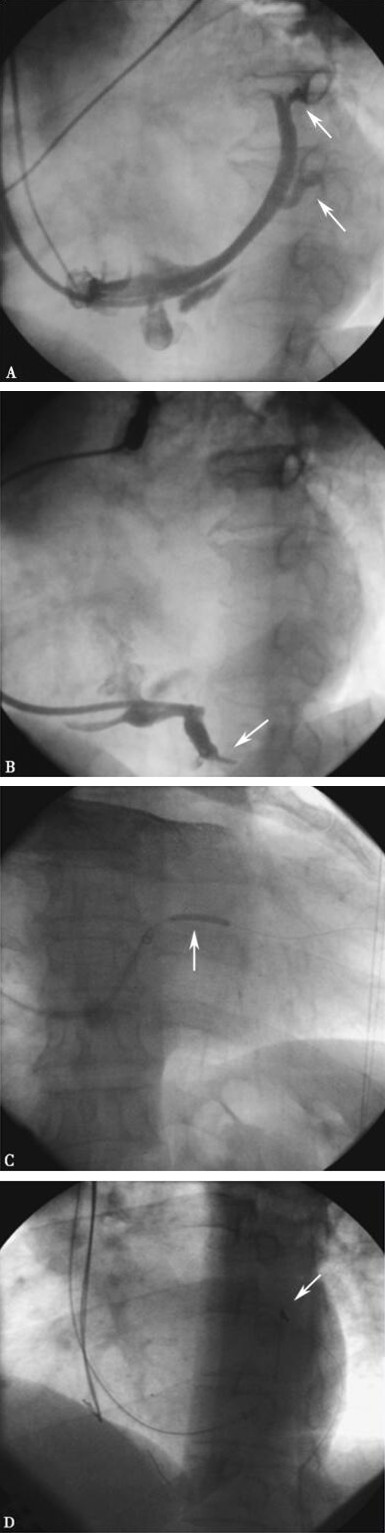

图3-4-13 冠状静脉造影、球囊扩张、电极植入影像

A:心侧静脉细小、心后侧静脉开口狭窄弯曲;B:心中静脉弯曲;C:球囊扩张心后侧静脉;D:球囊扩张后推送左室电极(1056,ST. Jude Medical),仍不能送入血管远端

诊断:扩张型心肌病,心功能Ⅳ级。住院后经药物强化治疗,患者能平卧24小时,于2007年7月14日行CRT植入术。术中经心脏静脉造影显示心侧静脉细小,心后侧静脉和心中静脉开口狭窄伴弯曲,将0.014″宝马导丝送至心后侧静脉远端,左室电极(1056型ST. Jude Medical)不能通过近端,Sprint 1.5mm × 15mm球囊送至狭窄段,4atm~20atm扩张数次,再用Grip 2.5mm × 16mm球囊送至狭窄段,以8atm~25atm压力扩张数次,造影示狭窄段扩张,但仍不能送入左室电极导线(图3-4-13),终止手术,CRT失败。